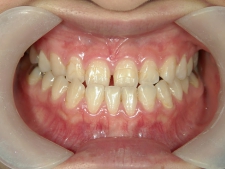

矯正歯科 治療前矯正歯科 治療前

主訴:受け口(反対咬合)を治したい

矯正歯科 治療前 急速拡大装置で上顎を広げた後、ワイヤーへ移行 非抜歯

no.31_7964_治療前_右 .JPGno.31_7964_治療前_正面 .JPGno.31_7964_治療前_左 .JPG